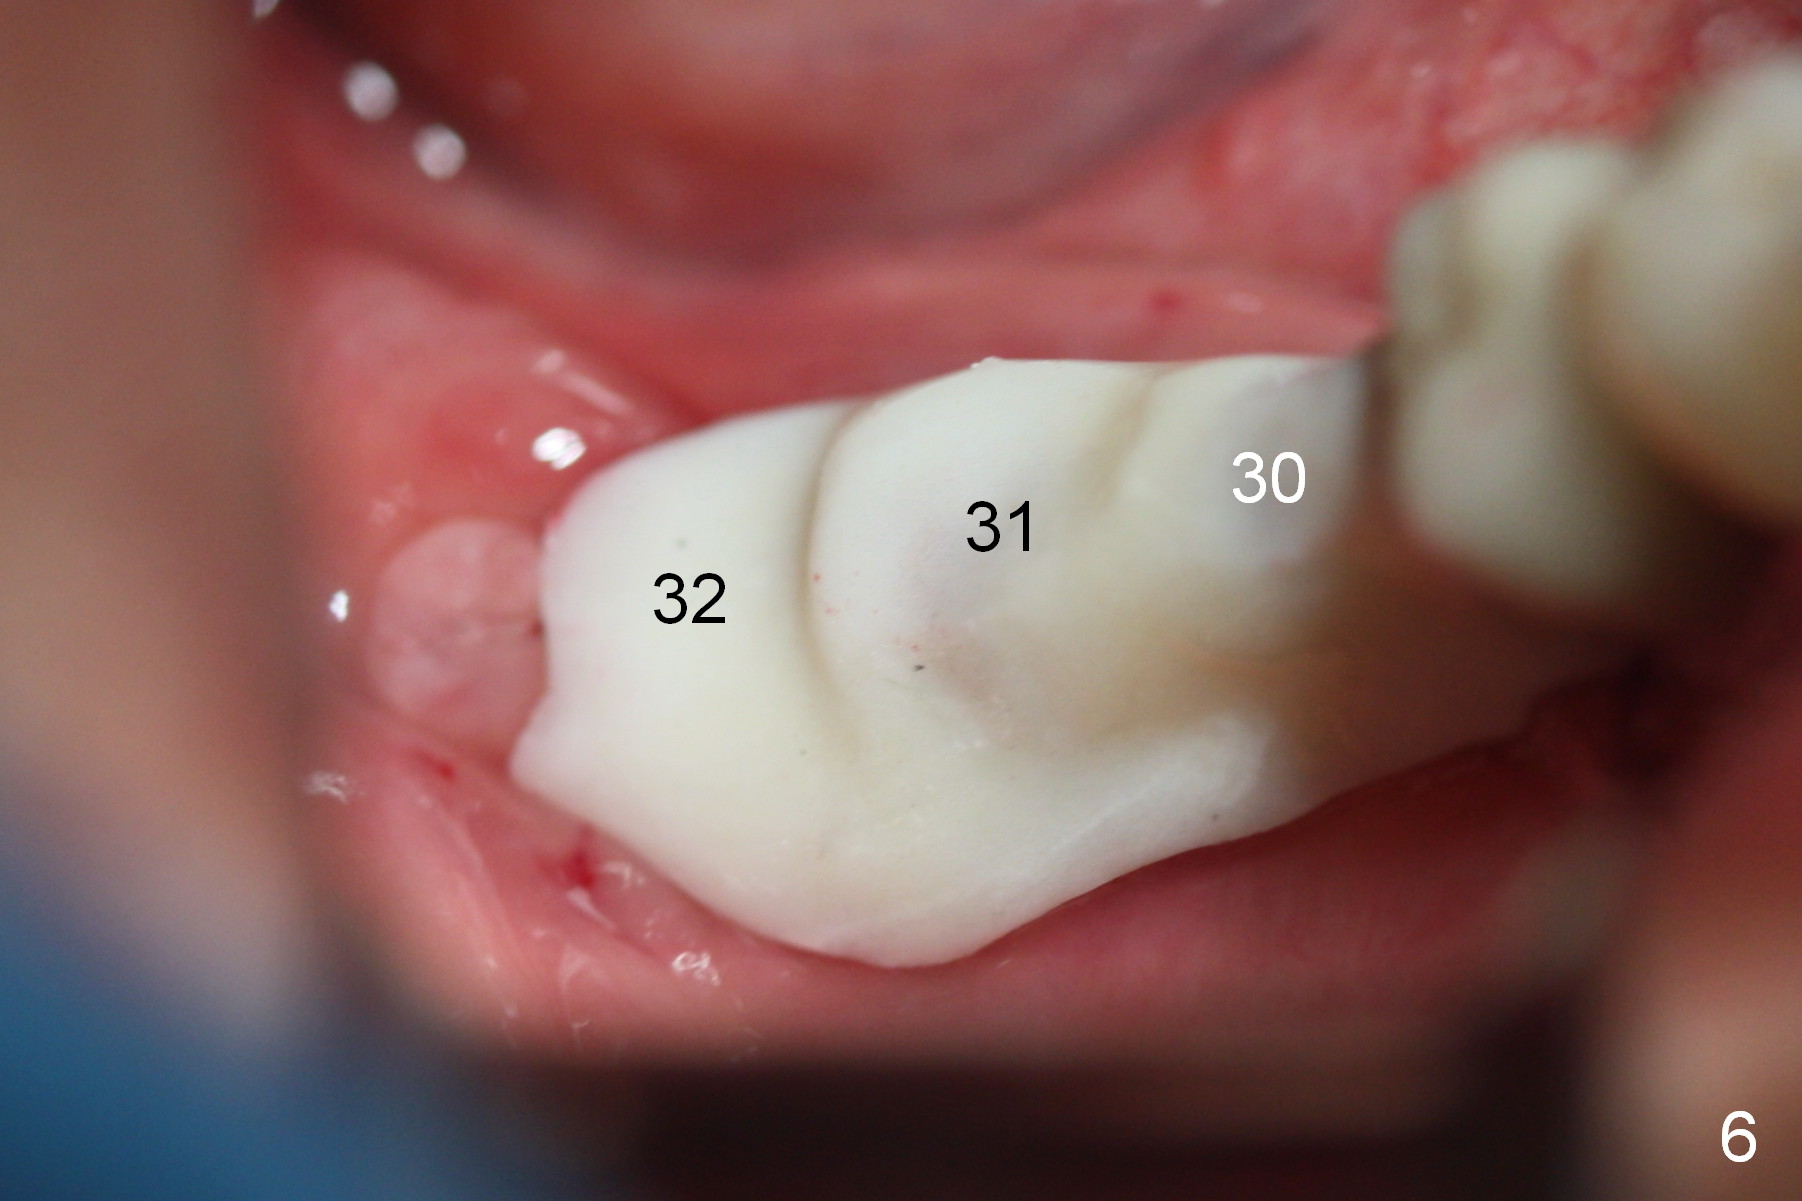

A preop photo shows different shape of pontics at #30 and 31 (Fig.1 <), suggesting different width of the edentulous ridge. Two of 8 mm parallel pins are inserted for position and trajectory (Fig.2 (red dashed line: the superior border of the Inferior Alveolar Canal). When they are removed from the osteotomy sites, the narrow ridge at #30 is shown (Fig.3). A 3x12 mm 1-piece implant is placed at #30, while a 4.5x10 mm 2-piece one at #31 (Fig.4,5). It appears that it is necessary to place an implant at #32, since the tooth #1 is present (Fig.5). The suggestion is rejected by the patient due to finance. After extraction of the tooth #32 and insertion of collagen plug, an immediate splinted provisional is fabricated to cover the #32 socket as well (Fig.6). The provisional is modified (to remove the portion that covers #32 socket) 3-4 weeks postop.